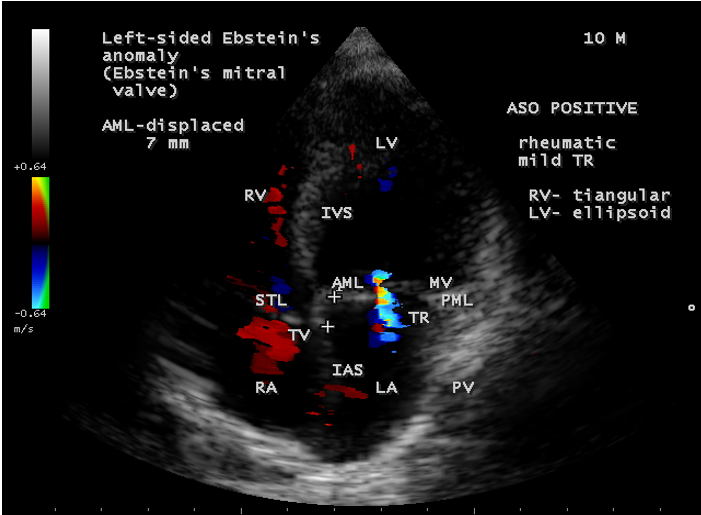

A 12- year old, asymptomatic boy was presented with features of an inverted Ebstein’s anomaly on routine echocardiographic screening as shown in

Figure 31 and the boy was advised periodic follow up.

Left-sided Ebstein’s anomaly

Ebstein’s anomaly of inverted tricuspid valve has been described in 15 -50% of cases of congenitally corrected transposition of great arteries [51] as in Figure 31. The anterior leaflet of inverted Ebstein’s anomaly is usually small, malformed and the atrialized inverted right ventricle is poorly developed, not thinned and rarely dilated [52]. The posterior wall of the inflow tract of the right ventricle is normal in inverted Ebstein (discordant atrioventricular connection)[53] and it is always abnormal in Ebstein’s anomaly of concordant connection in which the myocardium is replaced by fibrous tissue to variable degree. Rarely, a morphologic mitral valve (mMV)- right sided inverted mitral valve has anatomic features of Ebstein’s anomaly [54]. The leaflets tend to be thickened and even dysplastic in appearance [55]. Ebstein’s – like anomaly can also affect a normally positioned mitral valve as shown in Figure 32, although this is exceedingly rare, first reported by Rusahhaupt, et al in 1976 [56] and its embryologic origin is obscure [57]. The left atrioventricular valve incompetence is not necessarily caused by an Ebstein-like malformation, may be congenital and it is due to rheumatic involvement in this case. The anterior mitral leaflet (the aortic leaflet of mitral valve) is not particularly redundant, and its annulus inserts along the septum normally without downward displacement (offsetting). The normal ‘offsetting’ of the mitral and tricuspid valve is maintained in the four-chamber view [58]. Only the posterior leaflet, attached to the left ventricular free wall, is involved in downward displacement. Cases have also been reported in which both the mitral and tricuspid valves were involved by Ebstein’s malformation [59],[60].

Ebstein’s original case was an example of obstruction at the tricuspid orifice by a membrane dividing the right ventricle into two halves as shown in Figure 16 of a 28-year old cyanotic male with ECG and X-ray characteristics as in Figure 11 to 13. suggesting an advanced spectrum of Ebstein’s malformation , necessitating RV exclusion techniques such as Starnes’ procedure. The florid case of Ebstein’s anomaly with the insertion of leaflet tissue along with ventricular walls as a ‘blanket’ as in Figures 28 and 29 in a 30-year old cyanotic male may go for an initial palliation with bidirectional Glenn shunt (cavopulmonary anastomosis). The other variants of moderate degree of leaflet tethering with varying degrees of regurgitation, but an intact basal leaflet attachments with atrioventricular junction as in Cases 1 and 2 may need a definite repair. In Ebstein’s mitral valve as in Figure 32 in a 10-year old boy, the downward displacement of functional annulus > 0.8 cm/m2 is not particularly striking and tends to affect the septal leaflet (anterior mitral leaflet) alone. The valve is thickened and mildly regurgitant due to rheumatic involvement rather than an anatomic cause.